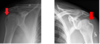

Osteocondroma

Exostose que cresce contráriamente à articulação

Cortical contígua com osso hospedeiro (medulares comunicam)

Pode ser pedunculado ou séssil